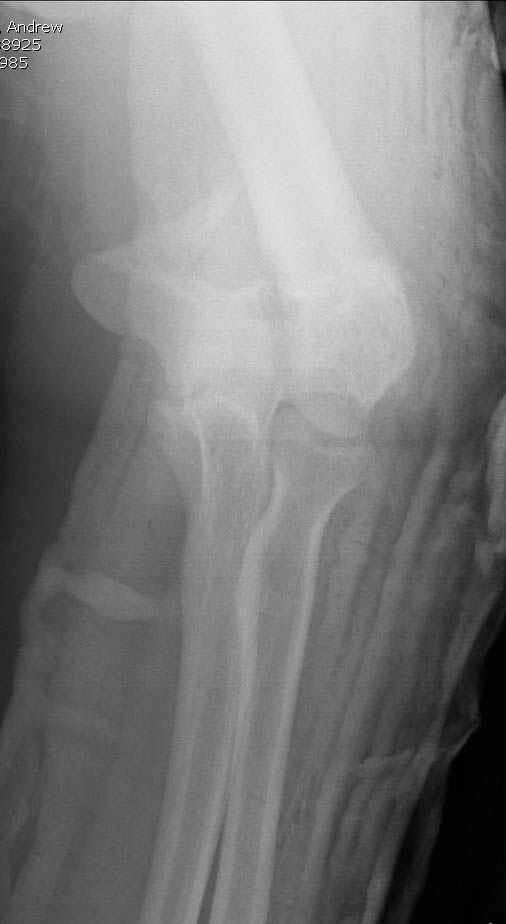

Примерный случай, только перелом был открытый, в задне-медиальной стороне рана около 2 см по характеру "изнутри кнаружи", неврологический статус со слабостью сгибания мизинца, также слабая абдукция и аддукция указательного пальца и сгибания в кисти.

Больному сделали обработку и наложили временный аппарат внешной фиксации плечо-предплечье.